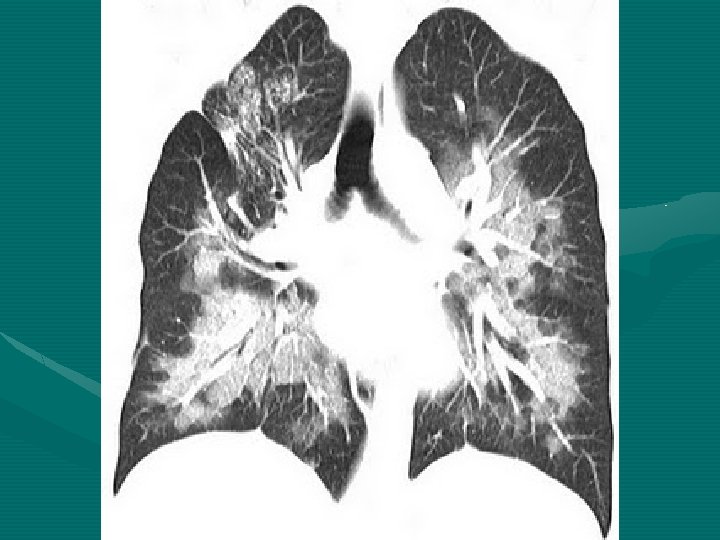

Síndrome da aspiração de conteúdo gástrico Ø Potencialmente fatal Ø Depressão de reflexos protetores da laringe → aspiração passiva ou ativa. Ø Gravidade: características físico-químicas Ø Sólidos: atelectasias; Ø Suco gástrico: > 25 ml e p. H< 2, 5 → pneumonite química Ø Obstrução intestinal, abdômen gestantes, cirurgia de emergência, TCE, álcool e drogas. Ø Suspeita clínica, exame físico e laboratoriais e radiográficos. agudo, obesos, achados

ØDispnéia, cianose, taquipnéia, roncos e sibilos. ØAnormalidades radiológicas: 90% Ø Lobo inferior direito; comprometimento bilateral Ø Medidas preventivas: ↑ o p. H e ↓ volume conteúdo gástrico Ø Antagonistas H 2; Metoclopramida. Ø Com aspiração: terapêutica de suporte: Pa. O 2 > 60 mm. Hg, aspiração traqueal ou